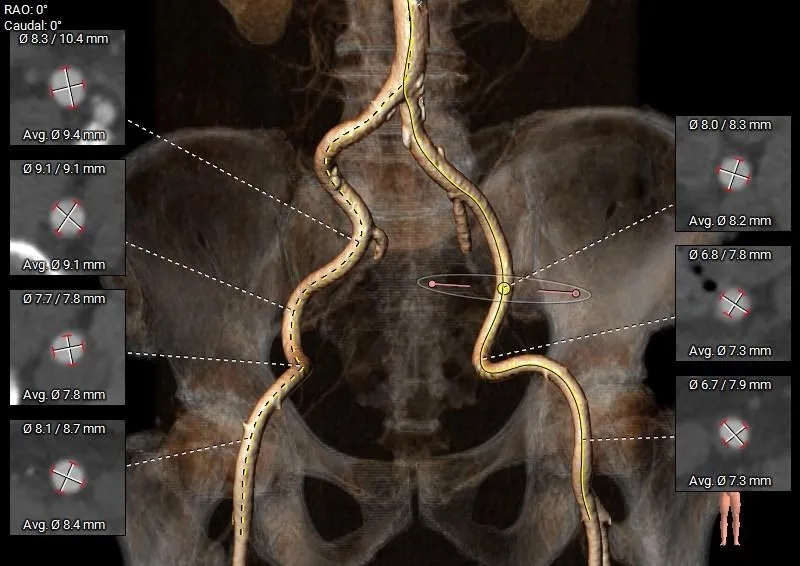

外周入路条件可

手术策略

经术前CT分析,该患者为三叶瓣(RN高位部分粘连),极重度钙化(钙化积分高达 1546mm³),窦部空间较小,冠脉开口层面可见冗长瓣叶,提示术中存在冠脉阻挡风险。面对该患者的特殊解剖挑战,经过多学科讨论,黄锋教授团队决定选用国产全可回收自膨式短瓣膜系统 ScienCrown为患者完成TAVI治疗。该瓣膜具备100%全释放&全可回收功能,可在手术过程中实现更充分的风险评估与更精准的瓣膜植入,若评估结果不佳可立即回收重做,是高冠脉风险病例的优选方案。

-

入路方式:右侧股动脉为主入路,左侧为辅入路;